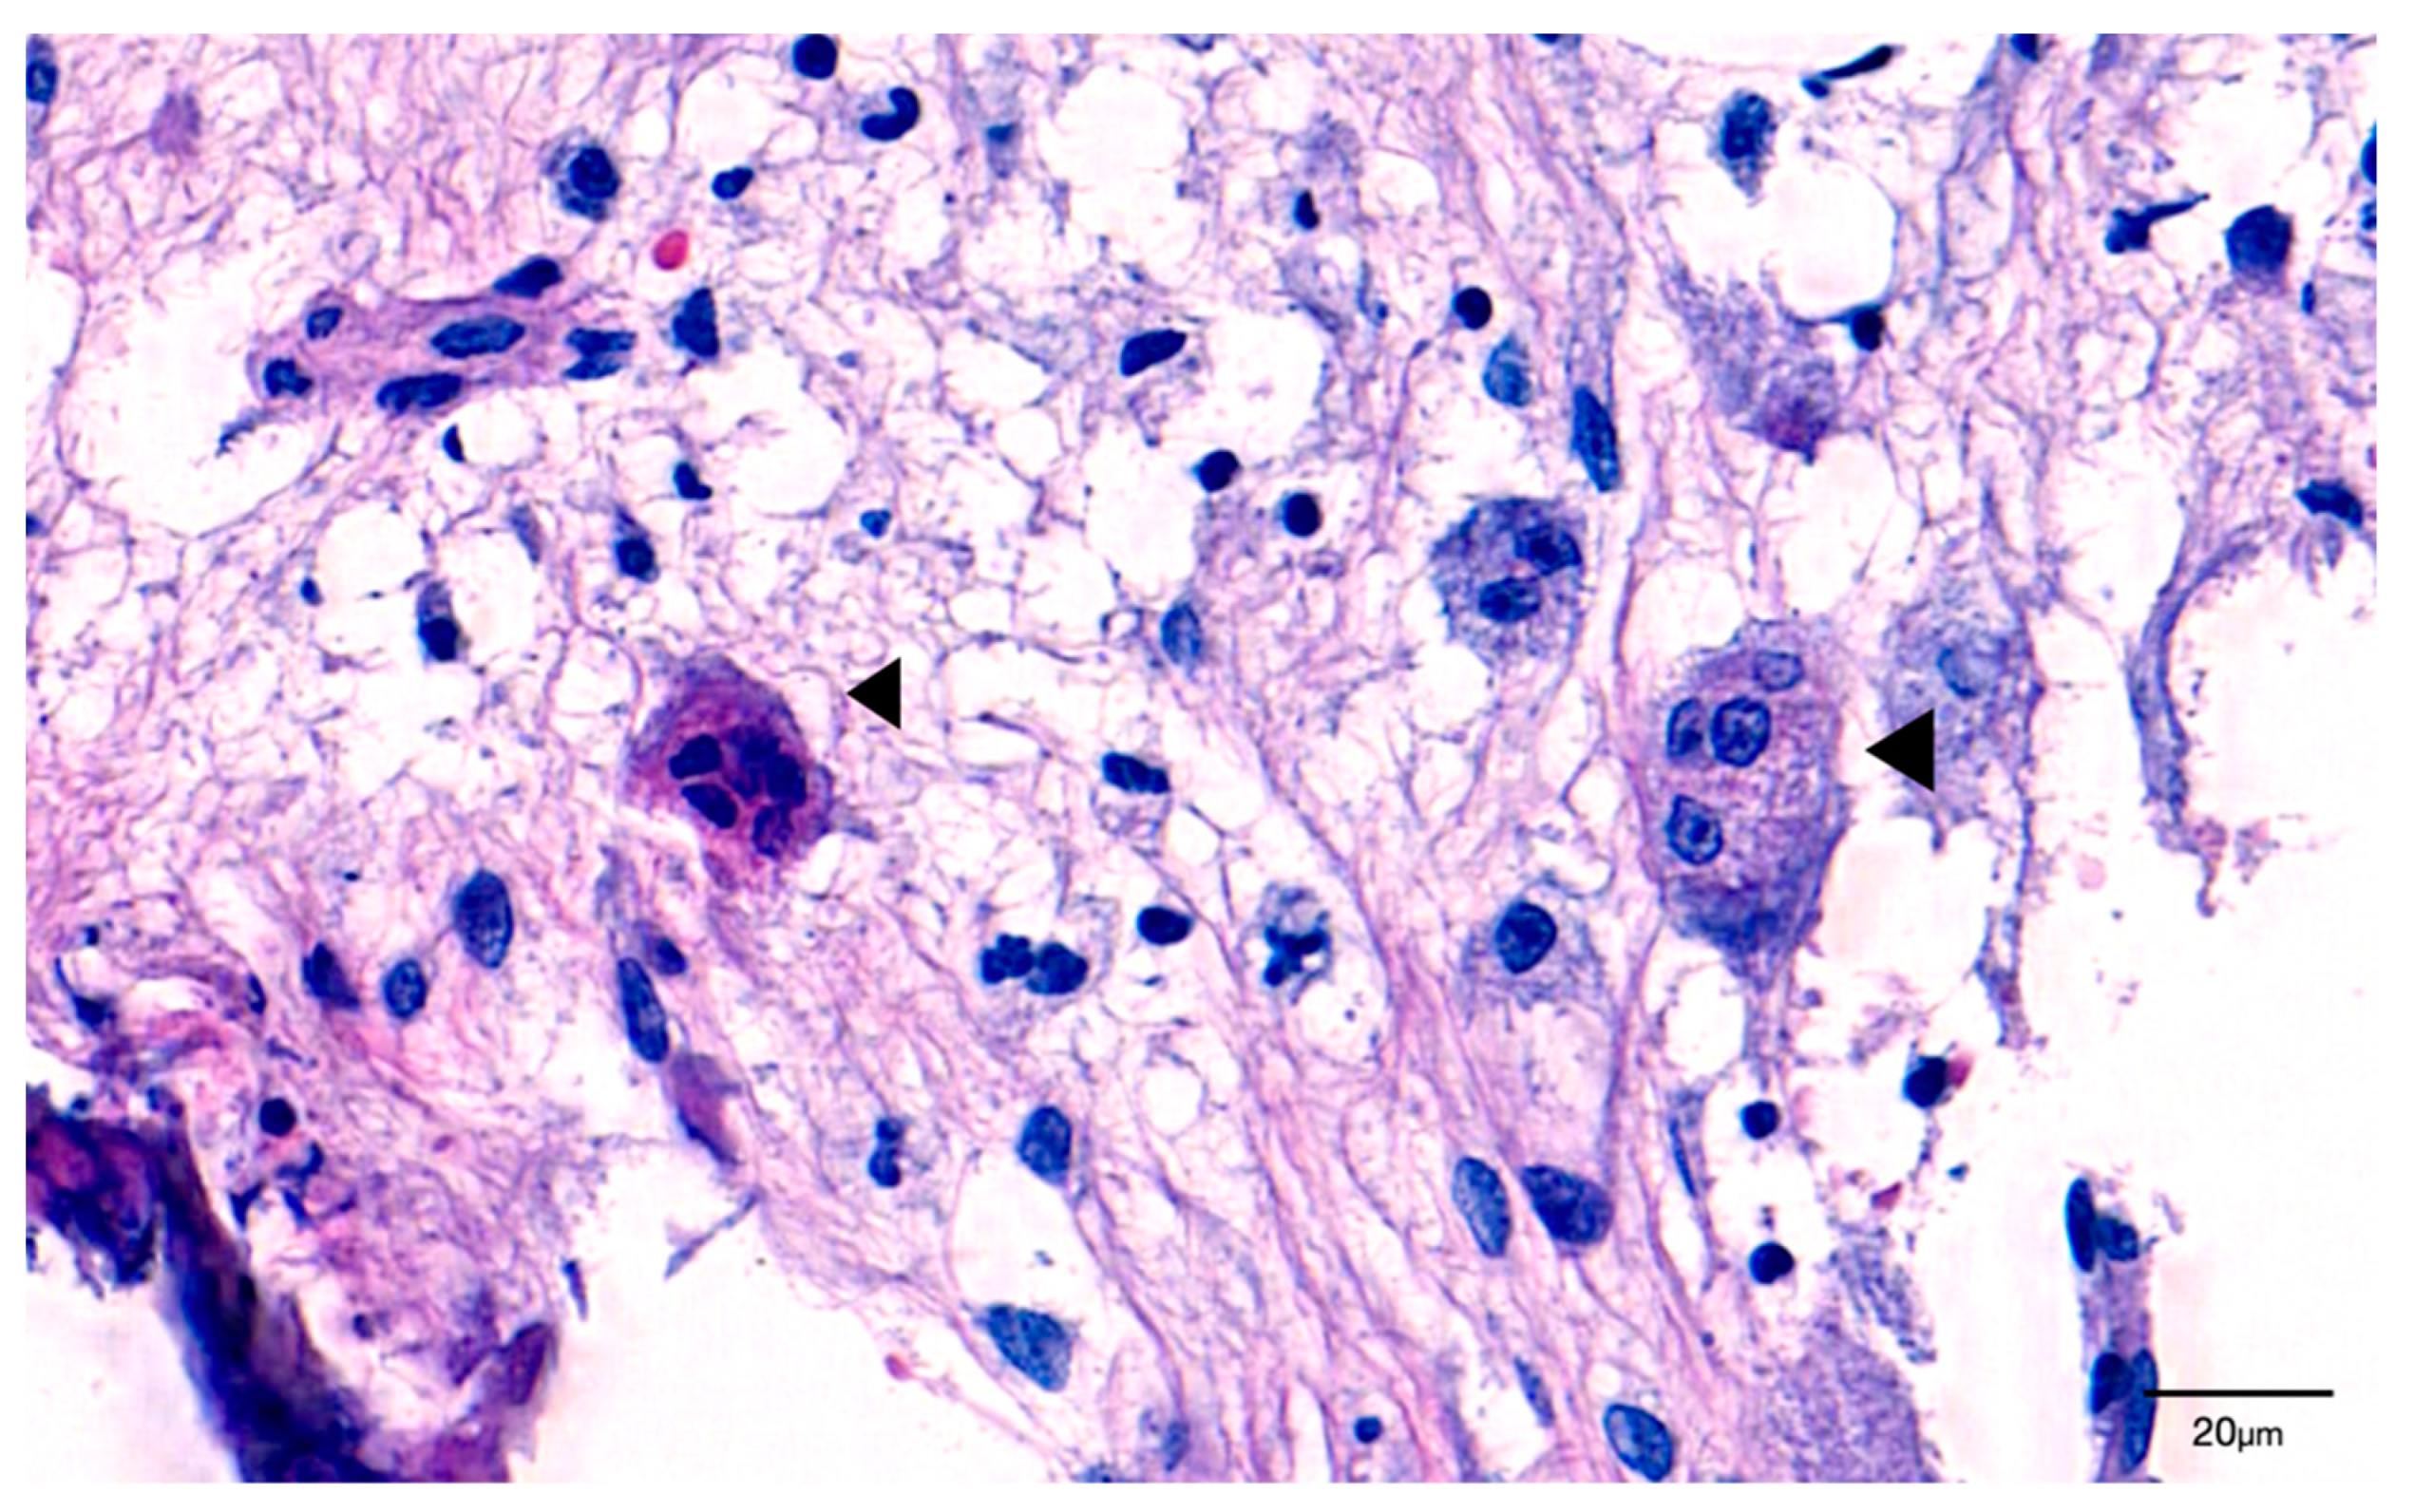

3.1.2. Tartrate-Resistant Acid Phosphatase (TRAP) Staining

- Weinstein, R.S.; Roberson, P.K.; Manolagas, S.C. Giant Osteoclast Formation and Long-Term Oral Bisphosphonate Therapy. N. Engl. J. Med. 2009, 360, 53–62. [Google Scholar] [CrossRef]

- Mac-Way, F.; Trombetti, A.; Noël, C.; Lafage-Proust, M.-H. Giant osteoclasts in patients under bisphosphonates. BMC Clin. Pathol. 2014, 14, 31. [Google Scholar] [CrossRef] [Green Version]

- Gross, C.; Weber, M.; Creutzburg, K.; Möbius, P.; Preidl, R.; Amann, K.; Wehrhan, F. Osteoclast profile of medication-related osteonecrosis of the jaw secondary to bisphosphonate therapy: A comparison with osteoradionecrosis and osteomyelitis. J. Transl. Med. 2017, 15, 1–14. [Google Scholar] [CrossRef]